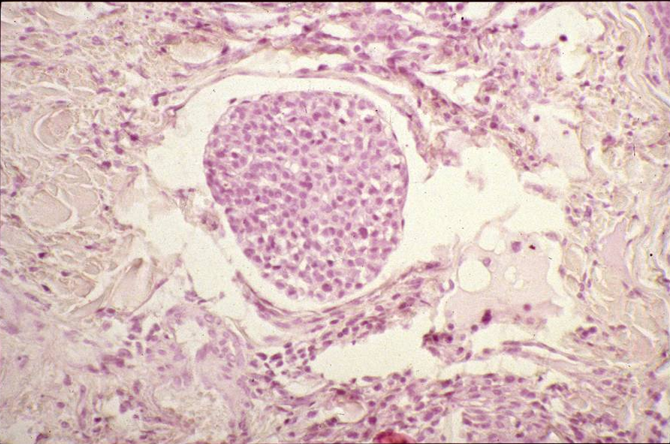

What does this show?

Tumour cell embolus within vein